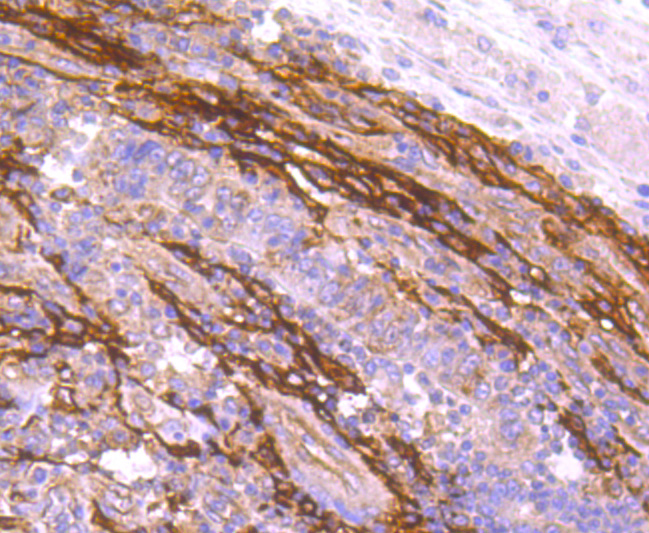

Immunohistochemical analysis of paraffin-embedded human colon cancer tissue using anti-FAP1 antibody. Counter stained with hematoxylin.

IHC: 1:50-1:200